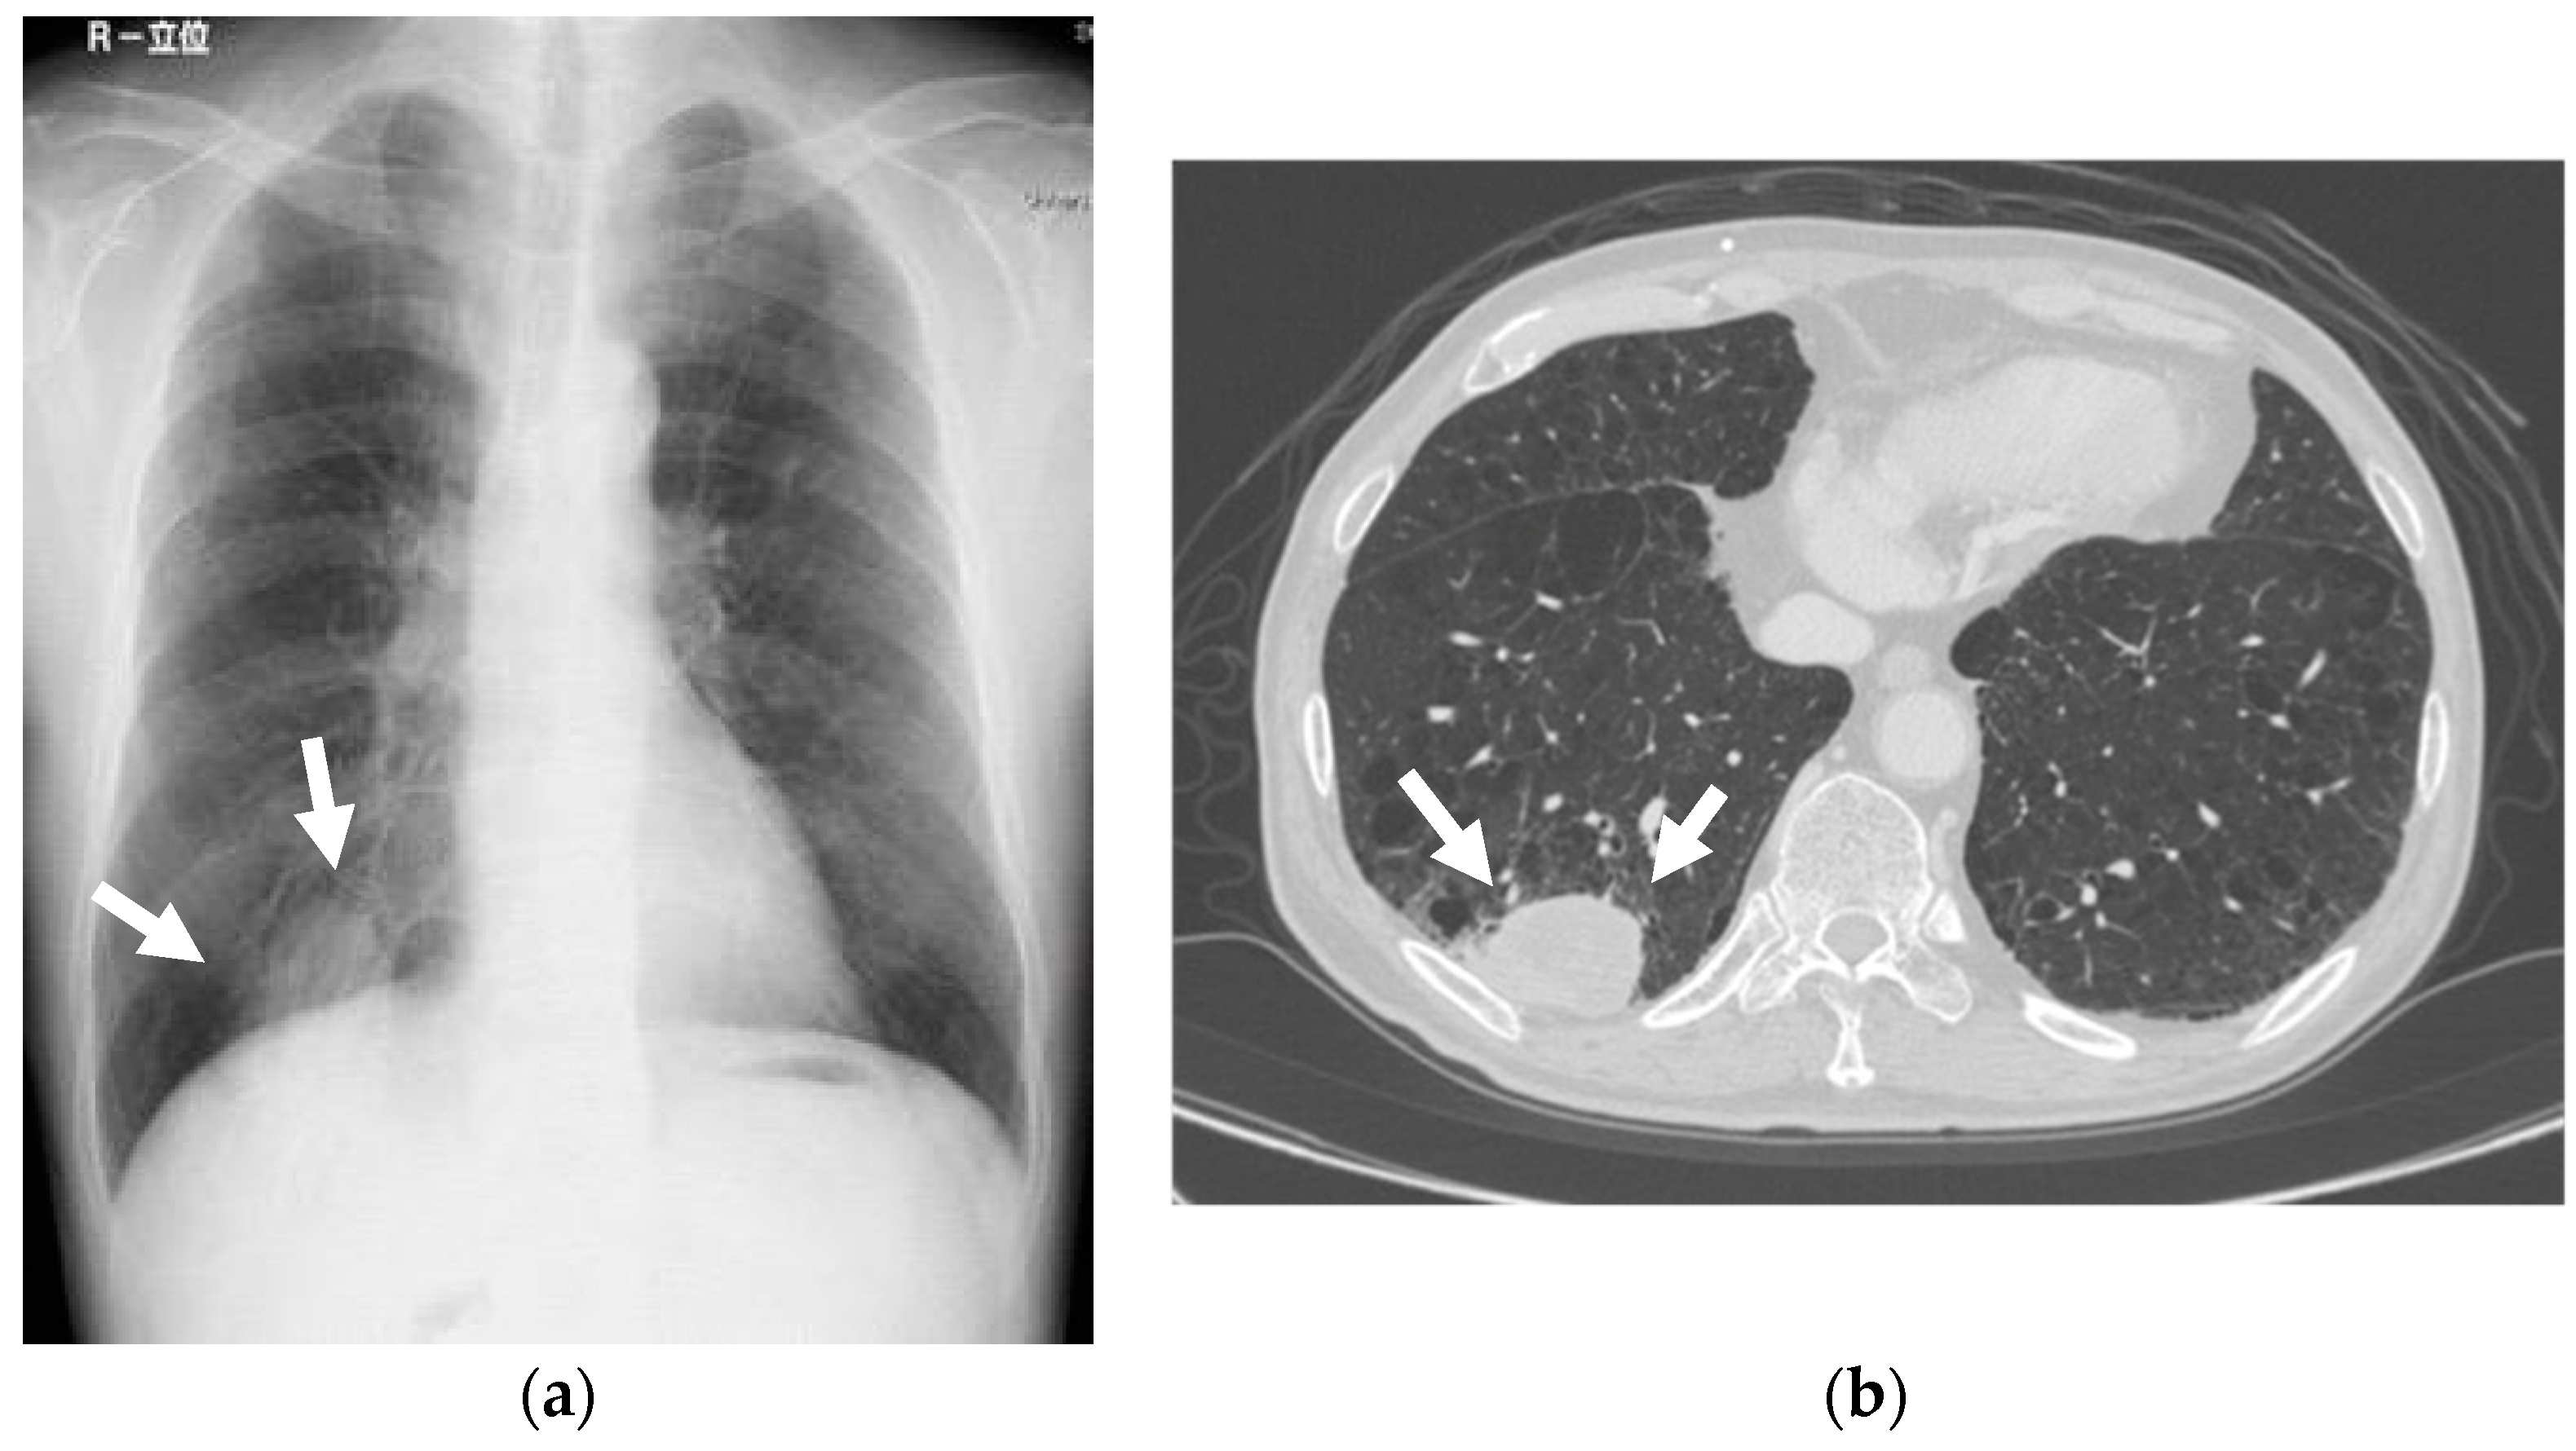

Short TI inversion recovery (STIR) sequence magnetic resonance imaging (MRI) showed a 34 × 31 × 21 mm heterogeneous, high-signal mass in the lower gingiva towards the floor of the mouth. Positron-emission tomography (18F-fluorodeoxy-glucose) combined with computed tomography (18F-FDG PET/CT) revealed the FDG uptake in the mass located at the lower gingiva, towards the floor of the mouth, with a standard uptake volume (SUV) max of 19.6. Chest X-rays revealed a 40mm, high-density mass nodule at the lower lobe of the lung. The CT depicted a high-density mass in the right S10, measuring 60 × 35 mm (Figure 2). The clinical diagnosis was lower gingival cancer (T4aN0M0, Stage IV) and lung cancer (T3N0M0, Stage IIA). At first, lung cancer was treated with thoracoscopic resection of the right inferior lobe and mediastinal lymph node dissection. The pathological diagnosis was squamous cell carcinoma (SCC), and the post-surgical course was uneventful. Chemoradiotherapy with a radiotherapeutic dosage of 41.4 Gy and administration of cetuximab for the gingival carcinoma started one month after lung surgery. After that, a supraomohyoid neck dissection, mandibulectomy, and reconstruction with a rectus abdominis musculocutaneous flap were performed under general anesthesia. The pathological diagnosis was SCC, and the post-surgical course was uneventful.

Figure 2.

Mass nodule. Chest X-rays revealed a 40 mm high-density mass nodule at the right lower lobe of the lung. The CT depicted a high-density mass in the right S10, measuring 60 × 35 mm. (a) Chest X-rays; (b) CT.